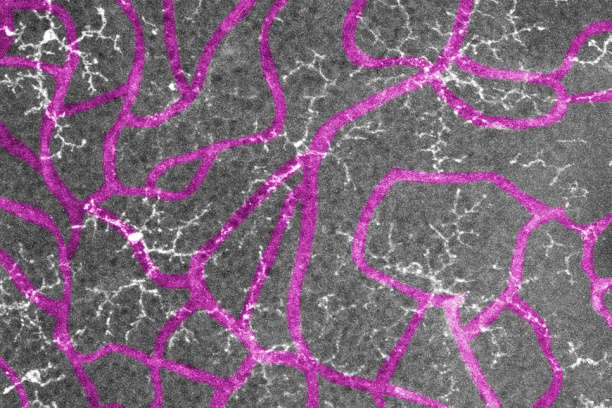

The goal of our research is to understand the roles that retinal neurons, in particular photoreceptors, play in the development of retinal vascular diseases such as diabetic retinopathy, age-related macular degeneration, and retinopathy of prematurity.

2. How do metabolic perturbations affect the "crosstalk" between retinal neurons, glia, and retinal vasculature?